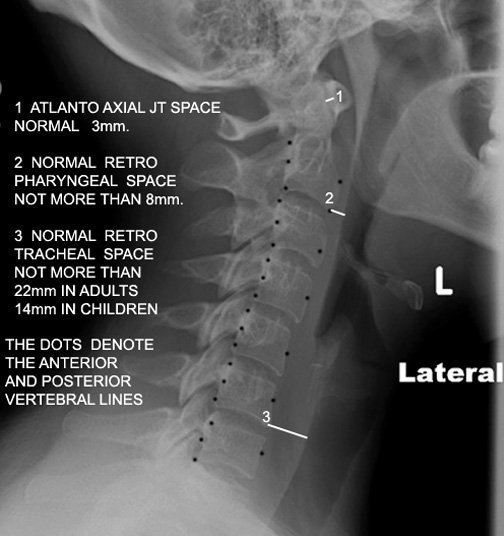

Identify the retrotracheal and retropharyngeal space. Click the image for labeling.